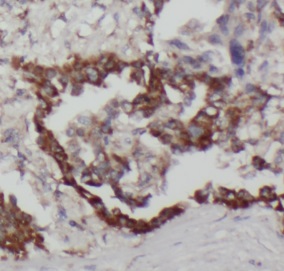

Immunohistochemistry of paraffin-embedded human lung cancer slide using FNab09112(TUSC4 Antibody) at dilution of 1:50 IP Result of anti-TUSC4 (IP:FNab09112, 3ug; Detection:FNab09112 1:500) with mouse pancreas tissue lysate 4000ug.